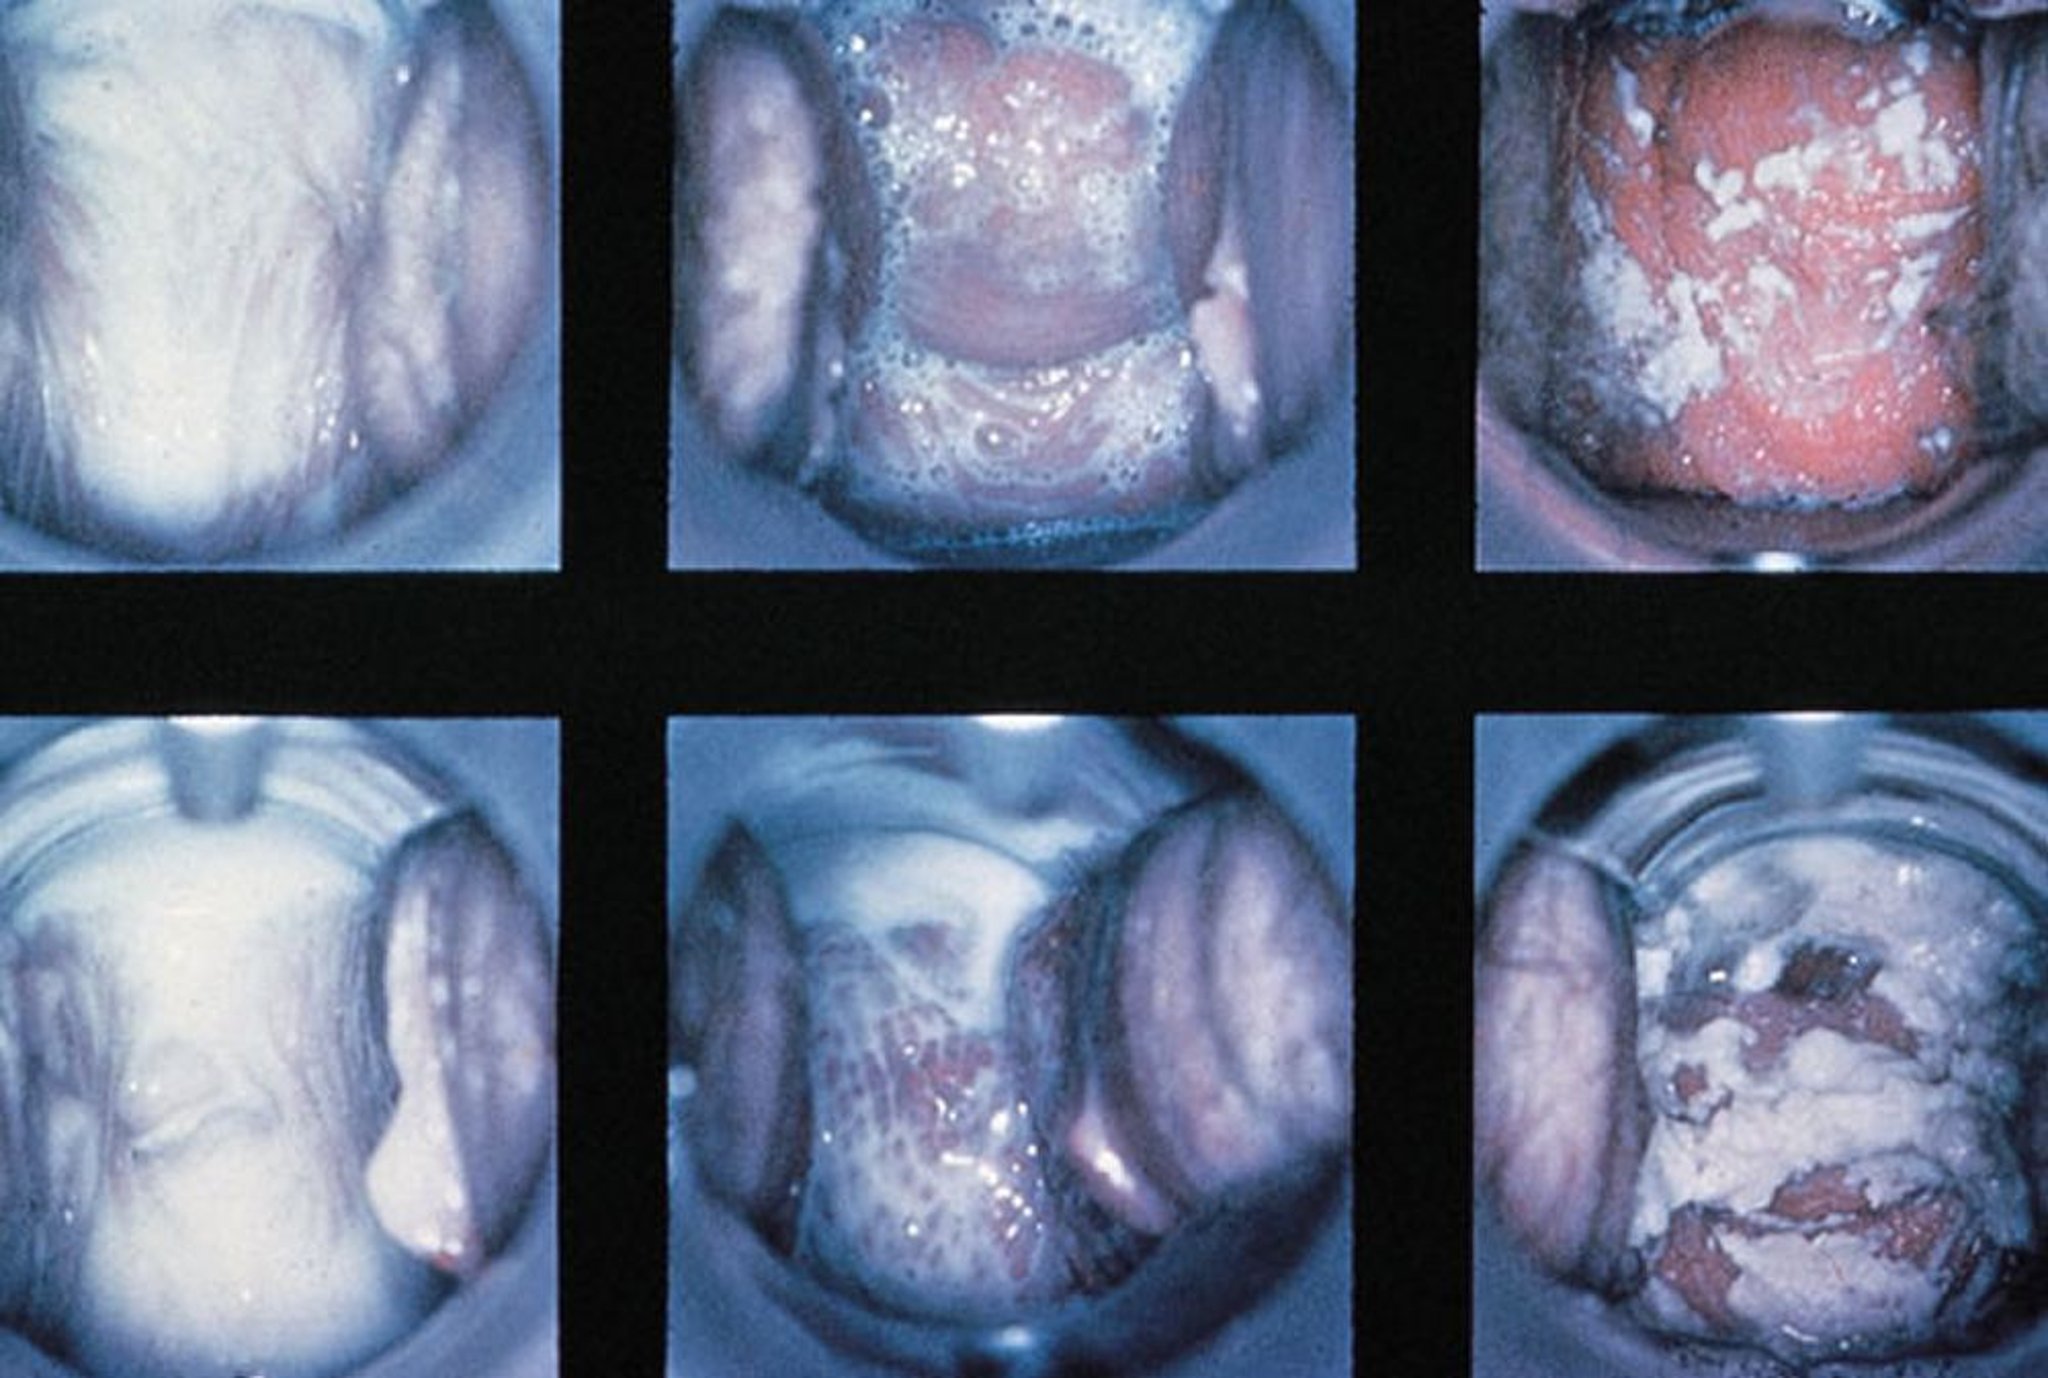

Speculum Examination in Vaginitis

Normal findings, trichomonal vaginitis with frothy discharge, and candidal vaginitis with thick, white discharge are shown (left to right).